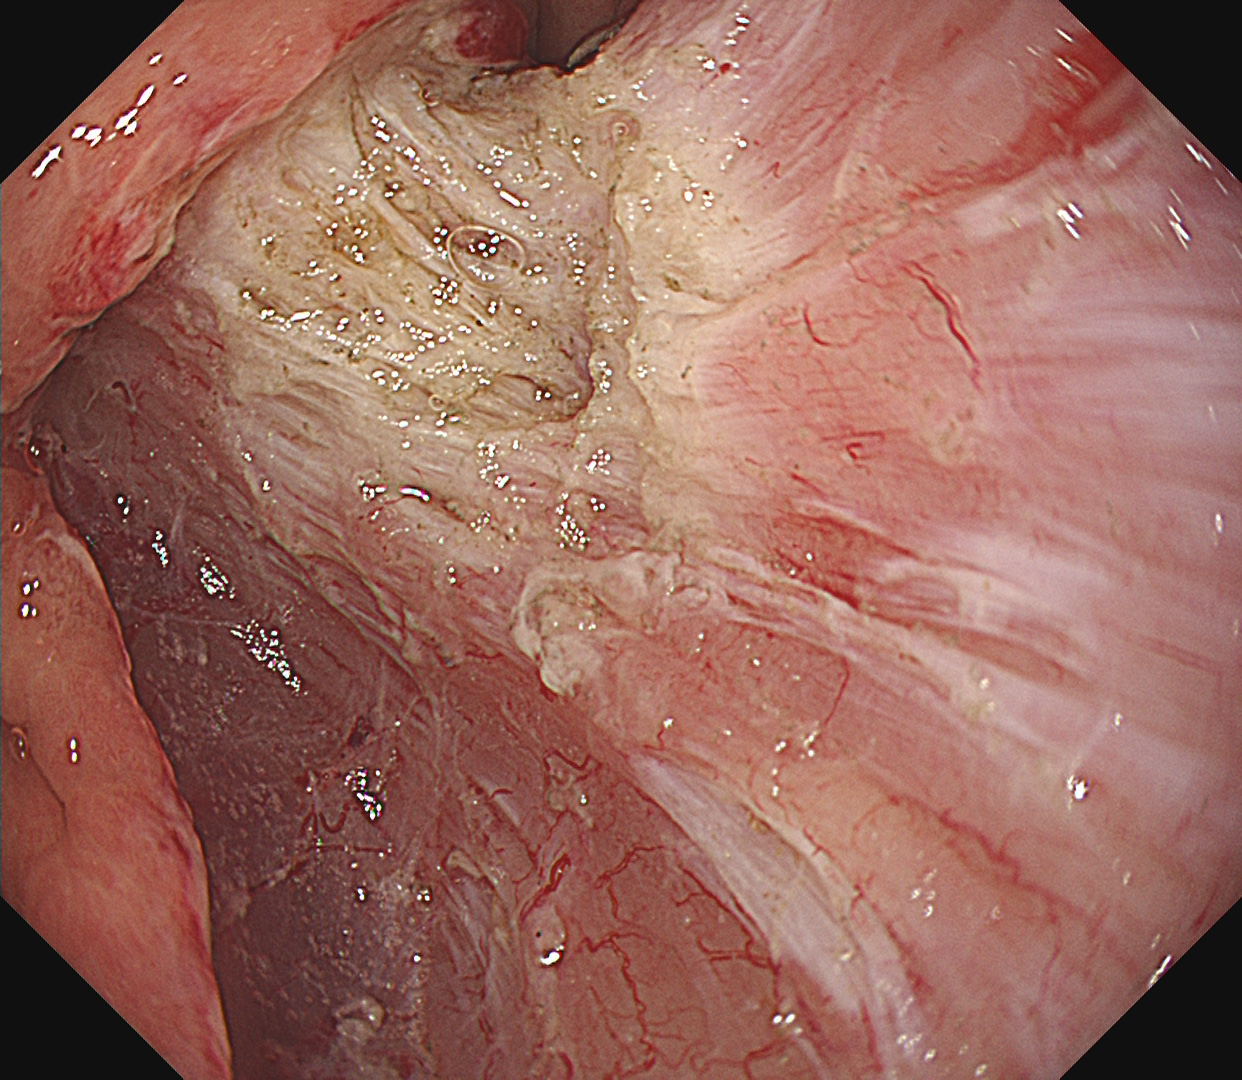

- EMR・ESD による早期消化管癌の低侵襲治療

- 咽頭・十二指腸・大腸を含む高難度 ESD に対応

早期胃癌(SM浸潤がん)ESD

早期大腸癌(LST-G)ESD